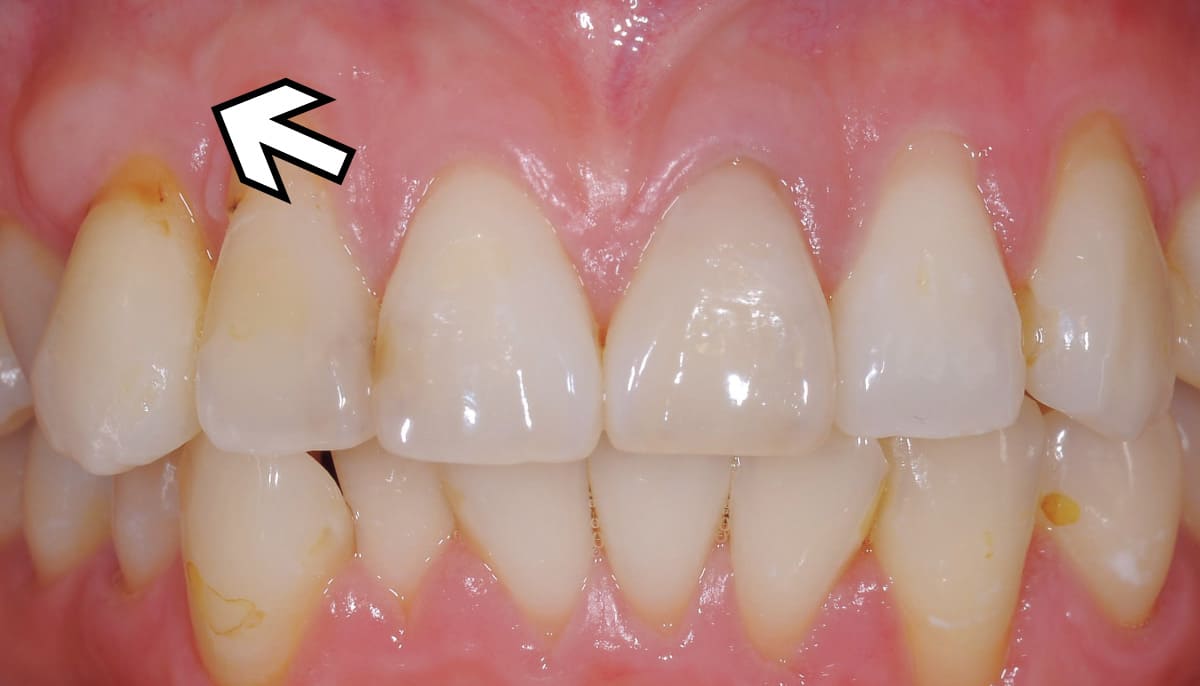

根面被覆|歯の根元の欠損部に自らの歯ぐきを移植。

Before

After

歯ぐきが下がって歯の根元が露出してしまった状態を改善する治療。最も多く行われているのは歯ぐきの移植。上顎の歯ぐきは切除しても再生するのでこの部分を患部に移植する。見た目はもちろん知覚過敏の改善にもつながる。

【料金】15万円〜

【治療期間】3か月〜6か月程度